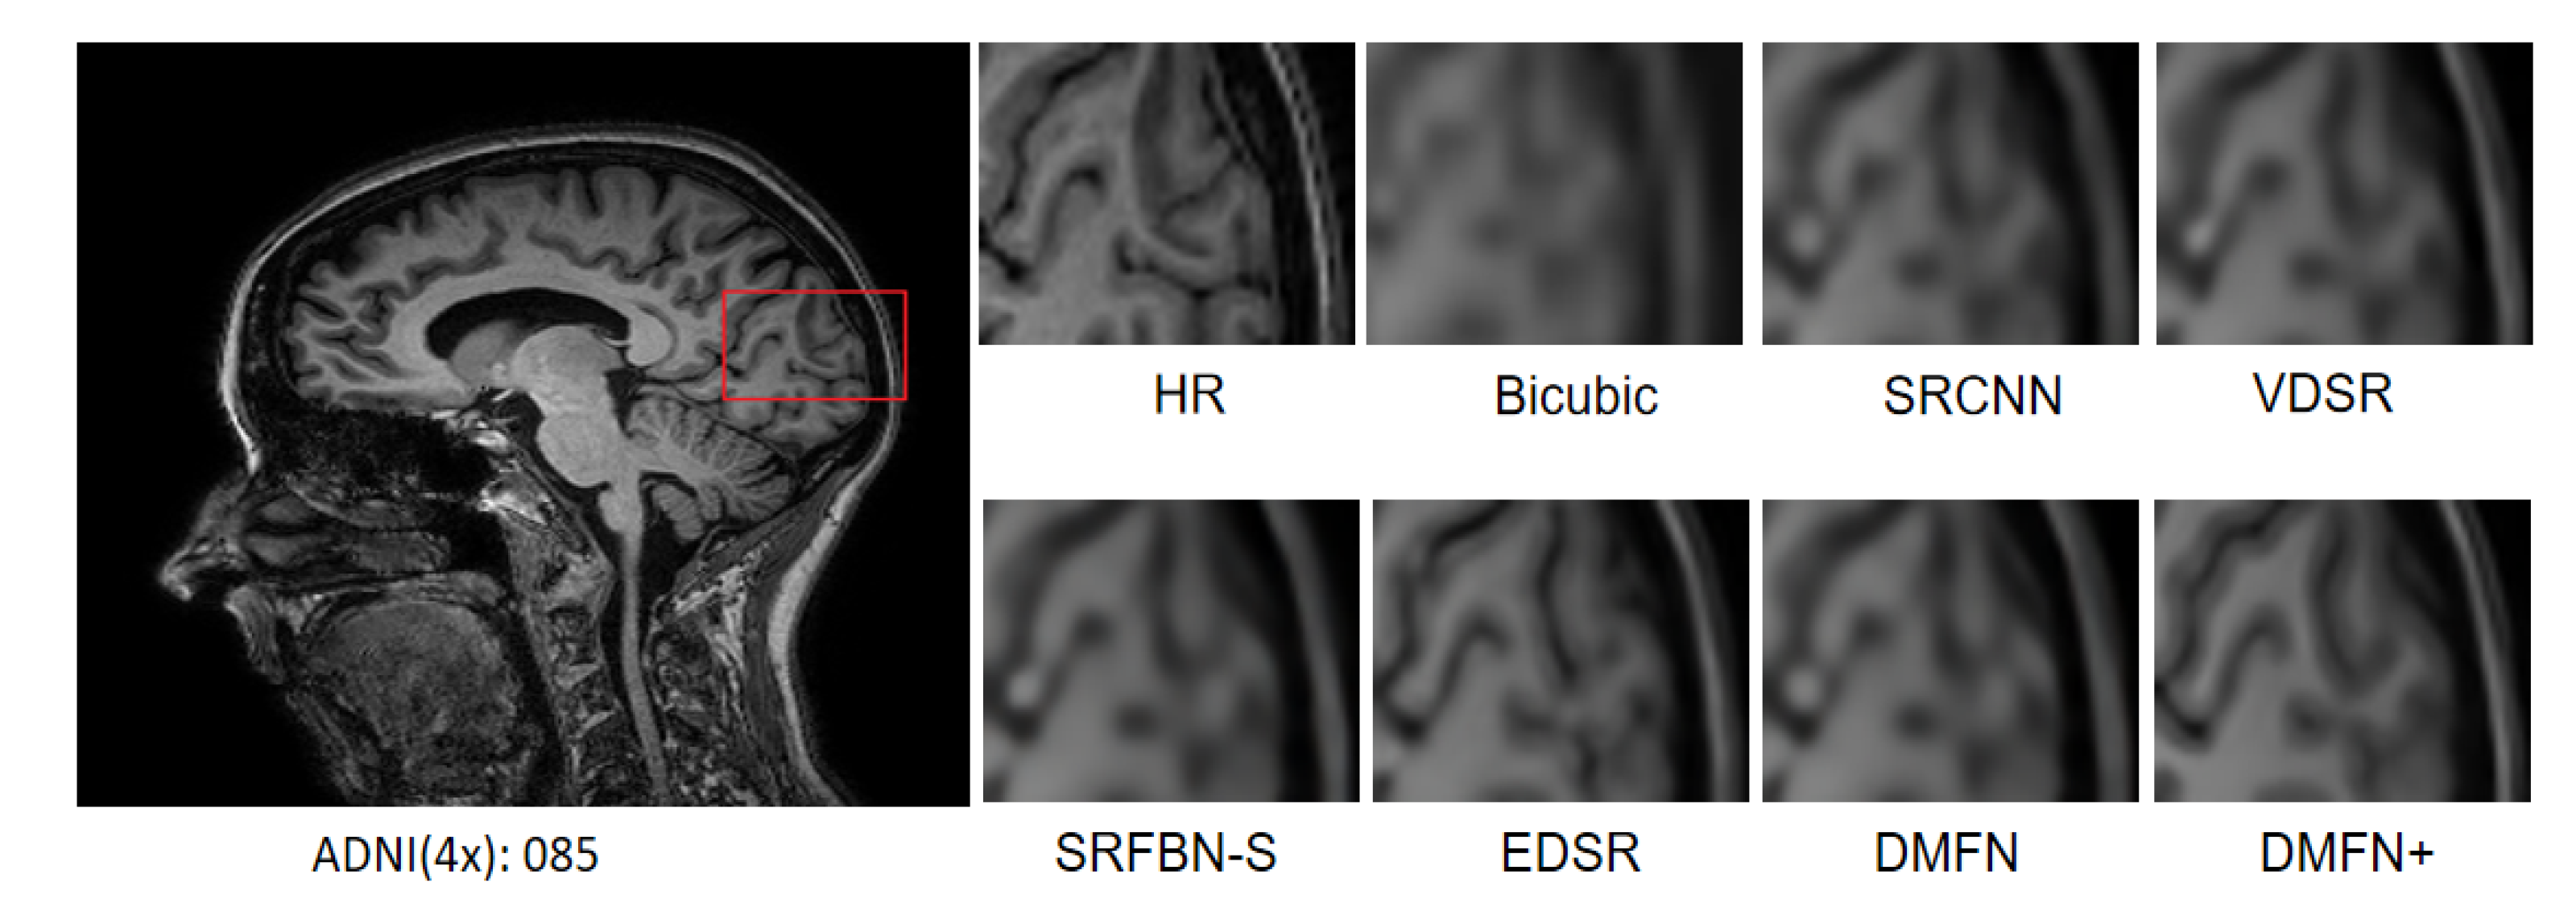

4.7. Comparison with Classical SR Methods

| Methods | Scale | Params | MRI13 | ADNI100 | OASIS100 |

|---|---|---|---|---|---|

| PSNR/SSIM | PSNR/SSIM | PSNR/SSIM | |||

| Bicubic | ×2 | - | 37.95/0.9677 | 30.74/0.8943 | 33.54/0.9585 |

| SRCNN [2] | 8 K | 40.76/0.9820 | 32.49/0.9258 | 35.52/0.9717 | |

| FSRCNN [5] | 13 K | 40.90/0.9809 | 40.90/0.9809 | 34.47/0.7778 | |

| VDSR [8] | 666 K | 41.78/0.9835 | 33.09/0.9328 | 36.70/0.9759 | |

| DRCN [9] | 1774 K | 42.15/0.9838 | 33.22/0.9336 | 37.19/0.9779 | |

| LapSRN [7] | 251 K | 41.99/0.9840 | 32.96/0.9317 | 36.98/0.9772 | |

| SRDenseNet [13] | 7160 K | 42.97/0.9846 | 33.33/0.9348 | 37.69/0.9788 | |

| DDSR [12] | 2020 K | 41.92/0.9833 | 33.00/0.9318 | 36.97/0.9766 | |

| EDSR [14] | 1370 K | 43.61/0.9853 | 33.50/0.9359 | 38.18/0.9797 | |

| SRMD [41] | 1511 K | 42.26/0.9841 | 33.15/0.9335 | 37.27/0.9780 | |

| SRMDNF [41] | 1511 K | 42.76/0.9848 | 33.30/0.9348 | 37.69/0.9794 | |

| SRFBN-S [21] | 282 K | 42.77/0.9843 | 33.29/0.9342 | 38.88/0.9806 | |

| FAWDN [22] | 7170 K | 43.35/0.9850 | 33.41/0.9352 | 37.91/0.9791 | |

| FAWDN+ [22] | 7170 K | 43.59/0.9851 | 33.87/0.9400 | 38.10/0.9798 | |

| DMFN(ours) | 475 K | 43.38/0.9850 | 33.41/0.9353 | 39.27/0.9813 | |

| DMFN+(ours) | 475 K | 43.57/0.9851 | 33.84/0.9397 | 39.43/0.9818 | |

| Bicubic | ×3 | - | 32.70/0.9126 | 27.95/0.8063 | 28.97/0.8919 |

| SRCNN [2] | 8 K | 35.03/0.9393 | 29.29/0.8527 | 31.27/0.9225 | |

| FSRCNN [5] | 13 K | 35.35/0.9406 | 29.48/0.8562 | 30.91/0.7568 | |

| VDSR [8] | 666 K | 35.43/0.9449 | 29.83/0.8661 | 31.60/0.9308 | |

| DRCN [9] | 1774 K | 35.83/0.9449 | 29.92/0.8672 | 32.18/0.9371 | |

| SRDenseNet [13] | 7160 K | 36.25/0.9469 | 30.06/0.8704 | 32.64/0.9477 | |

| DDSR [12] | 202 0K | 35.49/0.9433 | 29.68/0.8638 | 31.72/0.9330 | |

| EDSR [14] | 1555 K | 36.71/0.9484 | 30.27/0.8735 | 33.26/0.9444 | |

| SRMD [41] | 1528 K | 35.91/0.9456 | 29.91/0.8676 | 32.29/0.9385 | |

| SRMDNF [41] | 1528 K | 36.09/0.9465 | 30.02/0.8698 | 32.52/0.9405 | |

| SRFBN-S [21] | 375 K | 36.09/0.9459 | 29.99/0.8691 | 33.79/0.9453 | |

| FAWDN [22] | 7170 K | 36.60/0.9481 | 30.16/0.8719 | 33.00/0.9429 | |

| FAWDN+ [22] | 7170 K | 36.73/0.9479 | 30.75/0.8839 | 33.19/0.9450 | |

| DMFN(ours) | 583 K | 36.72/0.9485 | 30.17/0.8719 | 34.35/0.9478 | |

| DMFN+(ours) | 583 K | 36.75/0.9482 | 30.76/0.8843 | 34.41/0.9493 | |

| Bicubic | ×4 | - | 29.90/0.8591 | 26.37/0.7298 | 26.37/0.7298 |

| SRCNN [2] | 8 K | 31.75/0.8914 | 27.49/0.7838 | 28.47/0.8621 | |

| FSRCNN [5] | 13 K | 32.17/0.8934 | 27.66/0.7876 | 28.49/0.6900 | |

| VDSR [8] | 666 K | 32.44/0.9027 | 28.00/0.8028 | 28.96/0.8748 | |

| DRCN [9] | 1774 K | 32.64/0.9034 | 28.04/0.8029 | 29.29/0.8830 | |

| LapSRN [7] | 502 K | 32.68/0.9072 | 27.99/0.8027 | 29.26/0.8837 | |

| SRDenseNet [13] | 7160 K | 32.97/0.9075 | 28.18/0.8079 | 29.65/0.8900 | |

| DDSR [12] | 2020 K | 32.45/0.9029 | 27.91/0.8011 | 29.15/0.8798 | |

| EDSR [14] | 1518 K | 33.31/0.9107 | 28.42/0.8136 | 30.48/0.9003 | |

| SRMD [41] | 1552 K | 32.83/0.9060 | 28.05/0.8044 | 29.66/0.8884 | |

| SRMDNF [41] | 1552 K | 32.69/0.9062 | 28.13/0.8080 | 28.13/0.8080 | |

| SRFBN-S [21] | 483 K | 32.85/0.9069 | 28.20/0.8086 | 31.01/0.9006 | |

| FAWDN [22] | 7170 K | 33.22/0.9098 | 28.30/0.8117 | 30.05/0.8957 | |

| FAWDN+ [22] | 7170 K | 33.21/0.9086 | 28.81/0.8259 | 30.38/0.8895 | |

| DMFN(ours) | 707 K | 33.37/0.9104 | 28.30/0.8117 | 31.47/0.9051 | |

| DMFN+(ours) | 707 K | 33.33/0.9094 | 28.94/0.8310 | 31.54/0.9079 |